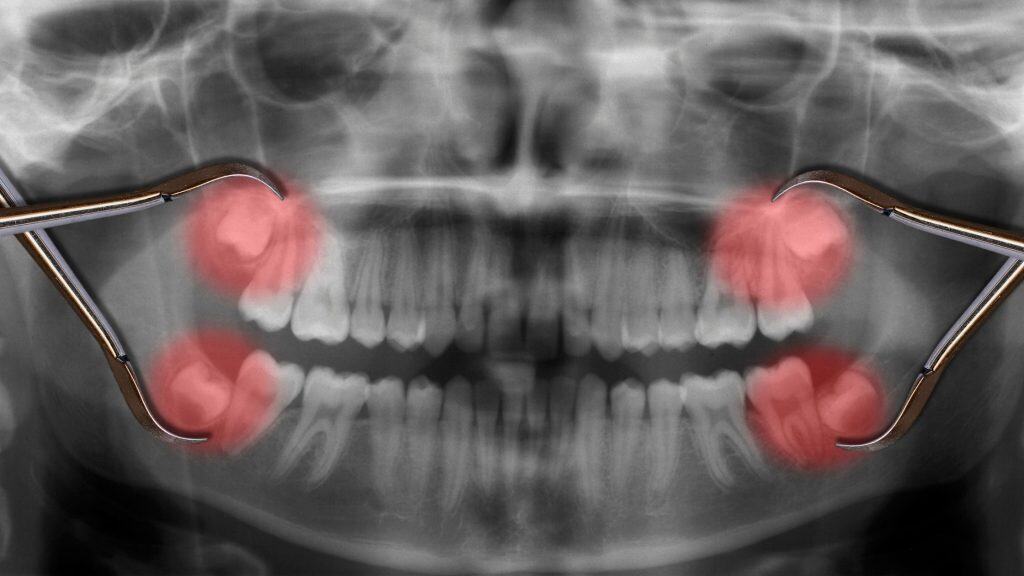

Wisdom teeth are the last set of adult molars to grow into the mouth. These molars usually erupt during a patient’s late teens or early 20’s. Most people grow in all 4 teeth, with 2 on the top and 2 on the bottom. However, some people grow in only 2 or 3. If wisdom teeth grow in right, they can be valuable to the mouth and may not require removal. However, most people must get these teeth extracted in order to prevent damage to the mouth.

The majority of the time, wisdom teeth grow in misaligned and require surgery for extraction. When the teeth grow in at an angle, this often results in painful crowding of the teeth, tooth decay, infection, and damage to the nerves and jawbone. This is why it’s important to get wisdom teeth removed before they begin to affect the the patient’s mouth structure and overall health.

In addition to misalignment, wisdom teeth can become impacted while growing in. This means that they are blocked by either soft tissue or the jawbone and only have the capacity to grow in partially. Due to this partial exposure, the area becomes prone to infection that causes in swelling, pain and stiffness of the jaw. With impacted wisdom teeth, the extraction is often done before the teeth begin to erupt in order to prevent any pain or swelling.

At A Smile 4 U, we pride ourselves in top, professional care for all of our patients. We’re confident we can provide you with a positive experience as you go through a wisdom teeth procedure. At your initial appointment, a dentist will diagnose the presence and position of your wisdom teeth with a panoramic x-ray. They will carefully evaluate the development and eruption of your wisdom teeth, ensuring that you have the most effective surgery for your case. When the time comes for your surgery, we recommend you go under general anesthesia which provides up to 6 hours of pain relief post operation. Before you are discharged, our staff will give you detailed instructions for a successful recovery at home.